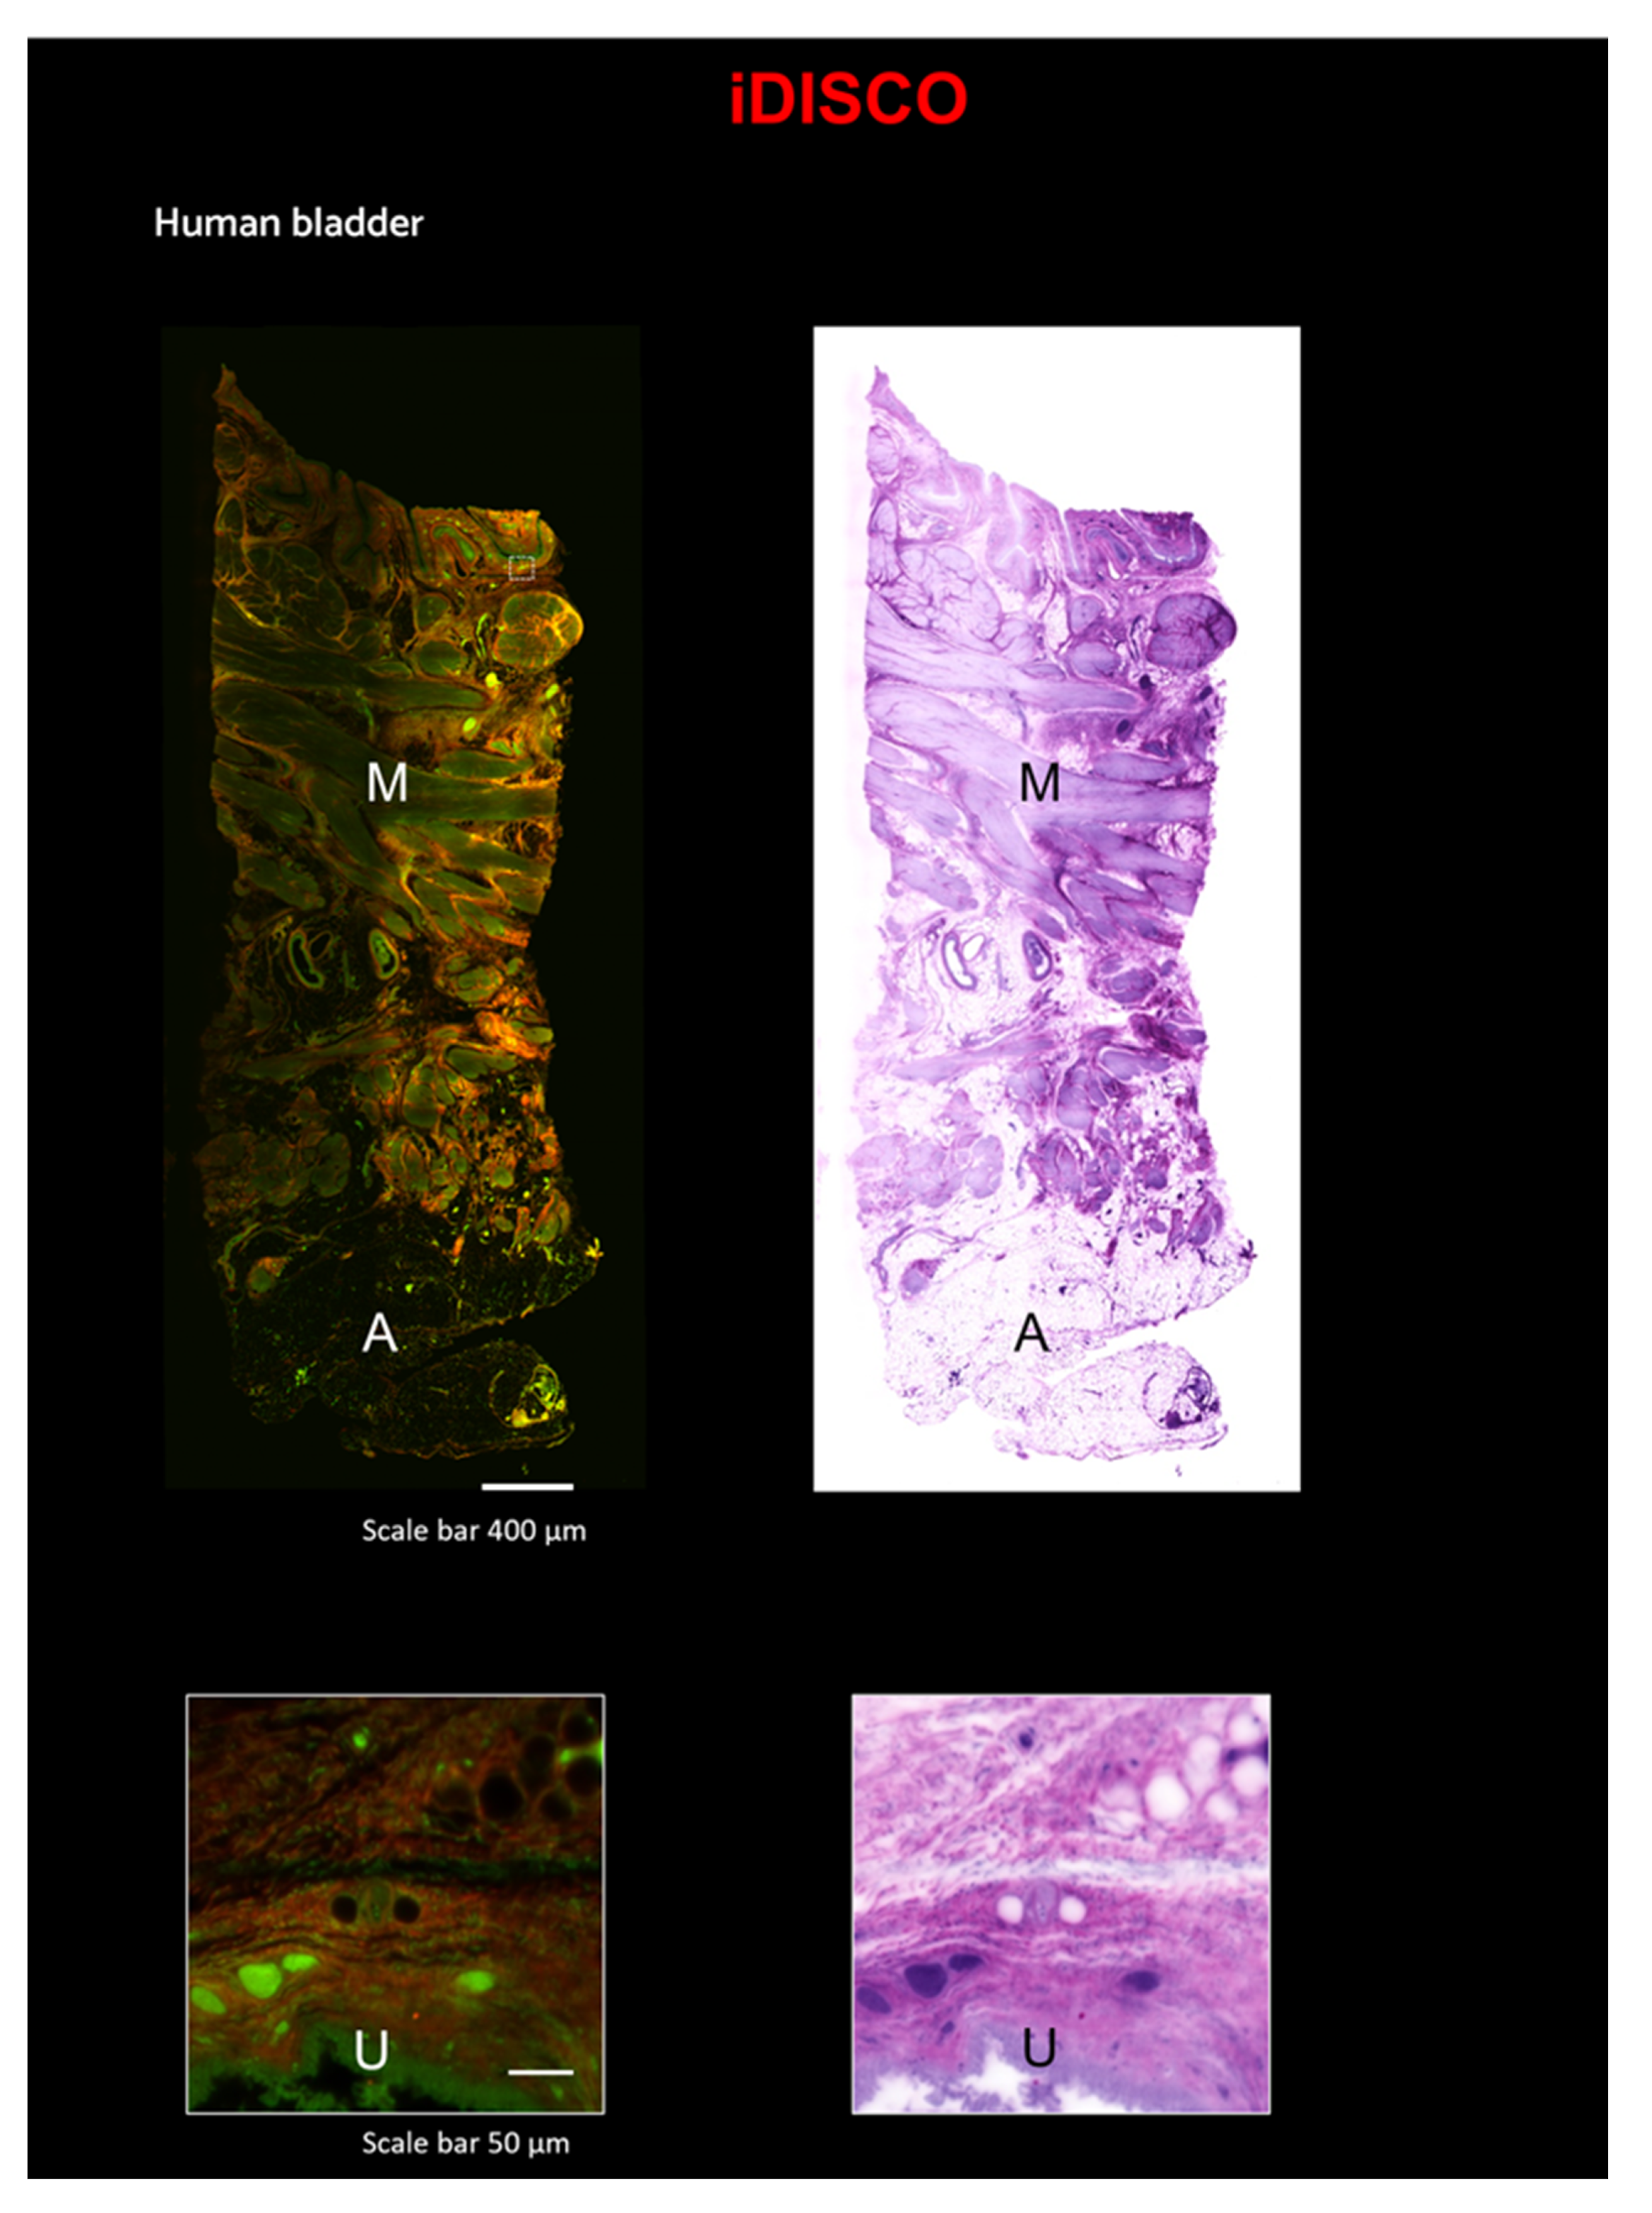

2.4. Eosin/SYTOX Blue Staining on iDISCO-Processed Sample